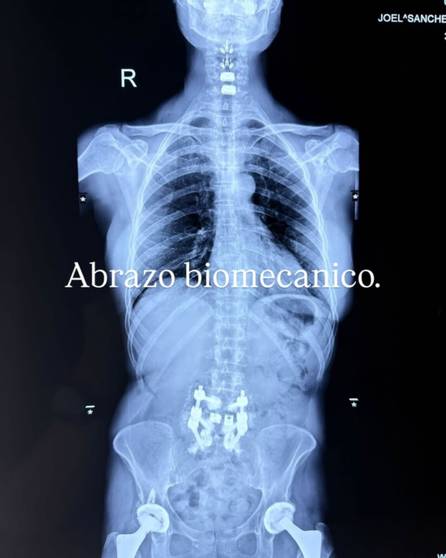

“Estoy muy contenta y agradecida con Dios y los procedimientos que me he sometido. El doctor me curó, me rehízo la columna vertebral, me hizo nuevas cervicales, nuevas lumbares, nuevos sacros. Estaba muy llena de Osteoporosis”, comentó tranquila.